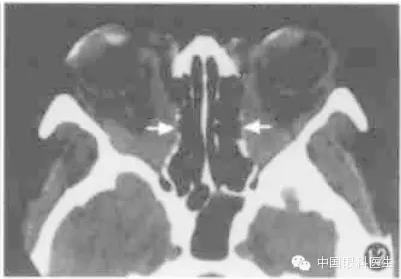

10.甲状腺相关眼病

甲状腺相关眼病也称Graves'病,这是最常见的单侧和双侧眼球突出原因。临床上有眼睑退缩、上睑迟落等一些典型体征。而CT在疾病的不同时期显示出不同的形态学的改变,主要CT征包括:眼球突出、眼外肌肥厚、脂肪垫扩大,其中以眼外肌肥厚最常见(图12)。其受累频率依次是下直肌、内直肌、上直肌和外直肌,晚期提上睑肌、上斜肌均肥厚。甲状腺相关眼病的眼外肌肥厚特征为以肌腹梭形肥厚为主,边界清楚。但当下直肌肥厚做水平CT扫描时,易误诊为眶内肿瘤,此时应做冠状CT鉴别。

图12甲状腺相关眼病CT显示双侧内外直肌肌腹和眶尖部增厚,视神经受压,筛骨纸板向内移位(箭头)